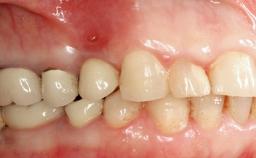

Management of a Fractured Implant Supporting a Screw-retained Metal-ceramic Restoration

The fracture of an implant after it has been restored is one of the most severe complications. It most frequently occurs in partially edentulous jaws (1.5%). Most implant fractures involve implants with a diameter of 3.75 mm made of commercially pure titanium (Eckert 2010). Unfortunately, many cases are not reported or documented by the clinicians involved in resolving the problems created by the fracture. This case report describes the management of an implant fracture at site 36 in a middle-aged male patient. The implant had been restored with a screw-retained metal-ceramic crown.